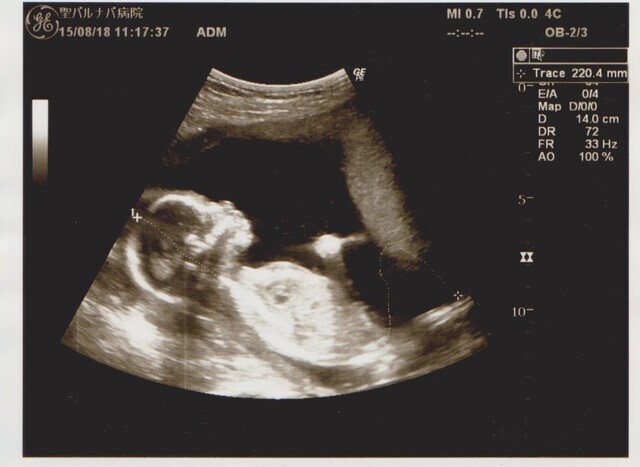

18週2日(18w2d・女の子)|まきはる65 さん(33歳)

エコー写真撮影時のエピソード:

里帰り出産先の病院で写してもらったエコー。綺麗な横顔がまるで影絵のようで、はっきりと人間らしくなっている様子に感動しました。妊娠報告をしてから初めての帰省で、結婚五年目にしてやっと授かった子であると同時に両家にとって初孫でとにかく皆が喜びでいっぱいで迎えてくれました